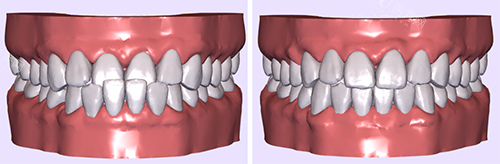

二、牙齿矫正价格

国产普特PT金属托槽矫正:5600元起

欧睛O-eyes金属自锁托槽矫正:8800元起

新亚Xinya陶瓷托槽矫正:11800元起

美国3M Clarity陶瓷自锁托槽矫正:14800元起

正雅Smartee隐形矫正(经典版):18800元起

时代天使Angelalign隐形矫正(冠军版):26800元起

美国隐适美Invisalign隐形矫正(标准版):32800元起

隐适美Invisalign Moderate中度矫正:35800元起

eBrace舌侧隐形矫正:38000元起

3M Incognito黄金舌侧隐形矫正:39000元起